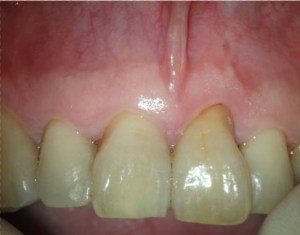

Después de realizarle un tratamiento de conductos  a la pieza 2.1 que presentaba una periodontitis apical crónica que fístulizaba, el paciente nos llegó los 4 meses con una nueva presencia de la fístula.

Con un aparente, buen tratamiento de conductos, estaría indicado una cirugía endodontica frente a este fracaso endodóntico por vía ortógrada, ya que necesitaríamos la ayuda de una obturación retrógrada.

Evaluamos el caso con un CBCT